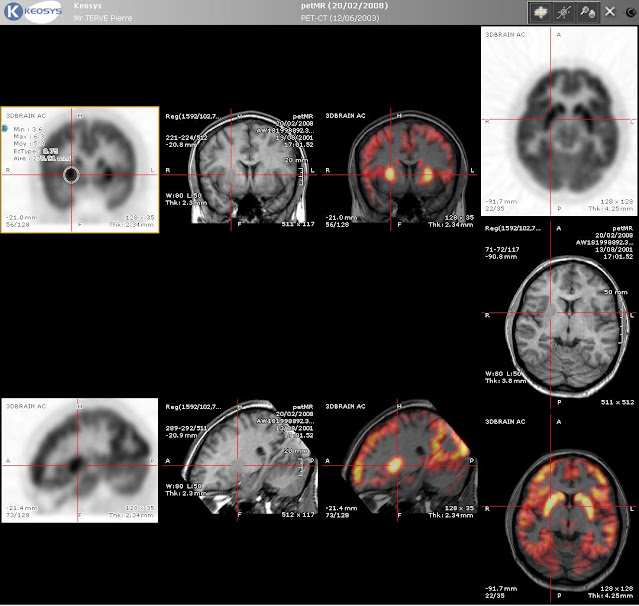

Pozytonowa tomografia emisyjna (ang. positron emission tomography, PET) jest najbardziej zaawansowaną techniką obrazowania stosowaną obecnie w medycynie. Wywodzi się ze scyntygrafii, w której do organizmu pacjenta wprowadzany jest preparat zawierający izotop radioaktywny, a następnie detektor bada jego rozmieszczenie w diagnozowanej tkance. W tym celu najczęściej wykorzystuje się izotopy emitujące promieniowanie gamma, np. jod-131 przy scyntygrafii tarczycy [LINK]. Z kolei w pozytonowej tomografii emisyjnej stosuje się izotopy ulegające rozpadowi beta plus. W tym rozpadzie jeden z protonów ulega przemianie w neutron z jednoczesną emisją neutrina i pozytonu. Liczba atomowa pierwiastka zmniejsza się o 1, czyli cofa się on o jedno miejsce w układzie okresowym. Liczba masowa pozostaje bez zmian, zatem powstały pierwiastek jest tzw. izobarem pierwiastka, z którego powstał. Poniżej porównanie rozpadu beta minus, który omawiałem niedawno [LINK] i beta plus (na dole)